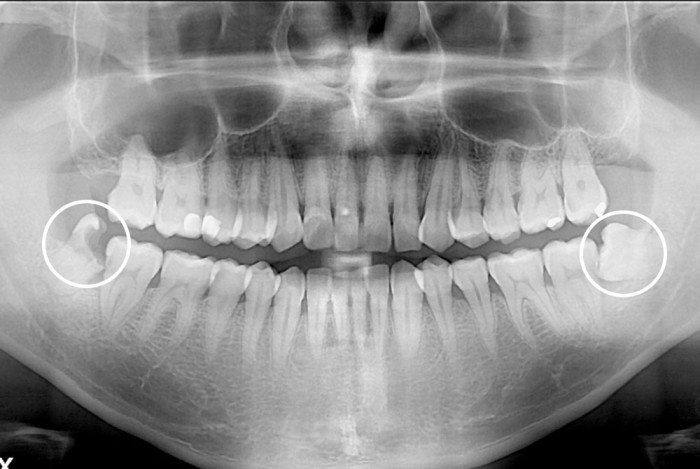

[사랑니] 사랑니

PX20191031_140959_0905_00000000.jpg

치료전 : 2019-10-31